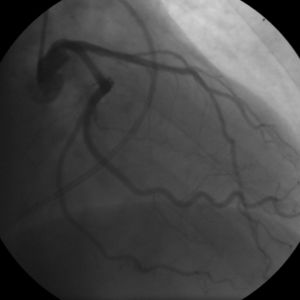

- Coronary angiography

الذبحة المستقرة

In "stable" angina, chest pain with typical features occurring at predictable levels of exertion, various forms of cardiac stress tests may be used to induce both symptoms and detect changes by way of electrocardiography (using an ECG), echocardiography (using ultrasound of the heart) or scintigraphy (using uptake of radionuclide by the heart muscle). If part of the heart seems to receive an insufficient blood supply, coronary angiography may be used to identify stenosis of the coronary arteries and suitability for angioplasty or bypass surgery.[17]

Diagnosis of acute coronary syndrome generally takes place in the emergency department, where ECGs may be performed sequentially to identify "evolving changes" (indicating ongoing damage to the heart muscle). Diagnosis is clear-cut if ECGs show elevation of the "ST segment", which in the context of severe typical chest pain is strongly indicative of an acute myocardial infarction (MI); this is termed a STEMI (ST-elevation MI) and is treated as an emergency with either urgent coronary angiography and percutaneous coronary intervention (angioplasty with or without stent insertion) or with thrombolysis ("clot buster" medication), whichever is available. In the absence of ST-segment elevation, heart damage is detected by cardiac markers (blood tests that identify heart muscle damage). If there is evidence of damage (infarction), the chest pain is attributed to a "non-ST elevation MI" (NSTEMI). If there is no evidence of damage, the term "unstable angina" is used. This process usually necessitates hospital admission and close observation on a coronary care unit for possible complications (such as cardiac arrhythmias – irregularities in the heart rate). Depending on the risk assessment, stress testing or angiography may be used to identify and treat coronary artery disease in patients who have had an NSTEMI or unstable angina.[بحاجة لمصدر]